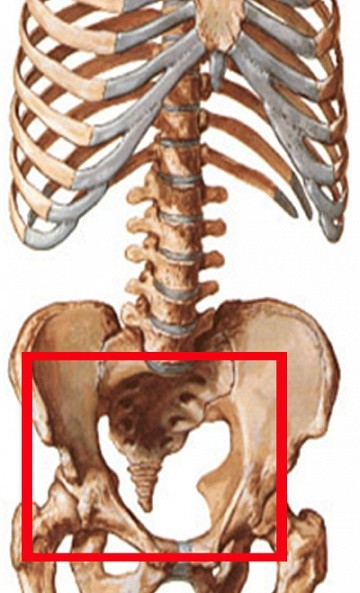

Нарушение функции суставов проявляется ограничением подвижности, хрустом, изменением походки, чувством «заклинивания» вплоть до полной невозможности движения – блокировки.

Деформация возникает за счет отека суставной сумки, разрастания остеофитов. При нарушении формы коленных суставов образуется Х- или О-образная деформация ног (рис. 4). При остеоартрозе пястно-фалангового сустава большого пальца стопы формируется пресловутая «косточка», которая уродует ногу и причиняет дискомфорт.

При неэффективности комплекса лекарственной и физиотерапии, ЛФК, стойком болевом синдроме и необратимой деформации суставов с ограничением подвижности, пациенту могут предложить операцию по замене сустава (эндопротезирование, рис. 5).